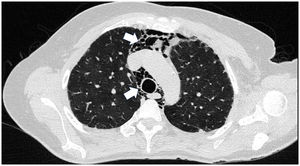

Hombre de 45 años con antecedente desde hace 2 años de DM con anticuerpos anti-MDA5 positivos con manifestaciones musculares y cutáneas clásicas de este fenotipo clínico (fig. 3), además de EPI tipo neumonía intersticial usual, la cual se había diagnosticado hacía 2 meses y por la que venía siendo tratado con ciclofosfamida 750mg IV única dosis. Consulta de forma espontánea por disnea súbita, razón por la cual se le realizó una angio-TAC (fig. 4) que demostró, además de la fibrosis pulmonar subyacente, neumomediastino y neumotórax de forma concomitante. Se procedió a realizar broncoscopia y estudios microbiológicos, los cuales fueron negativos, por lo que se decidió continuar con la siguiente dosis de ciclofosfamida, ciclosporina 3mg/kg/día e inicio de recambios plasmáticos. No obstante, en días posteriores, luego de iniciadas las terapias, el paciente presenta mayor deterioro respiratorio y desafortunadamente fallece a causa de la progresión y la exacerbación de la EPI, además de un aumento considerable de neumomediastino y neumotórax a pesar de haberle realizado toracostomías por parte de cirugía de tórax. Se consideró que todo el cuadro configuró un diagnóstico de EPI rápidamente progresiva y el paciente finalmente fallece.